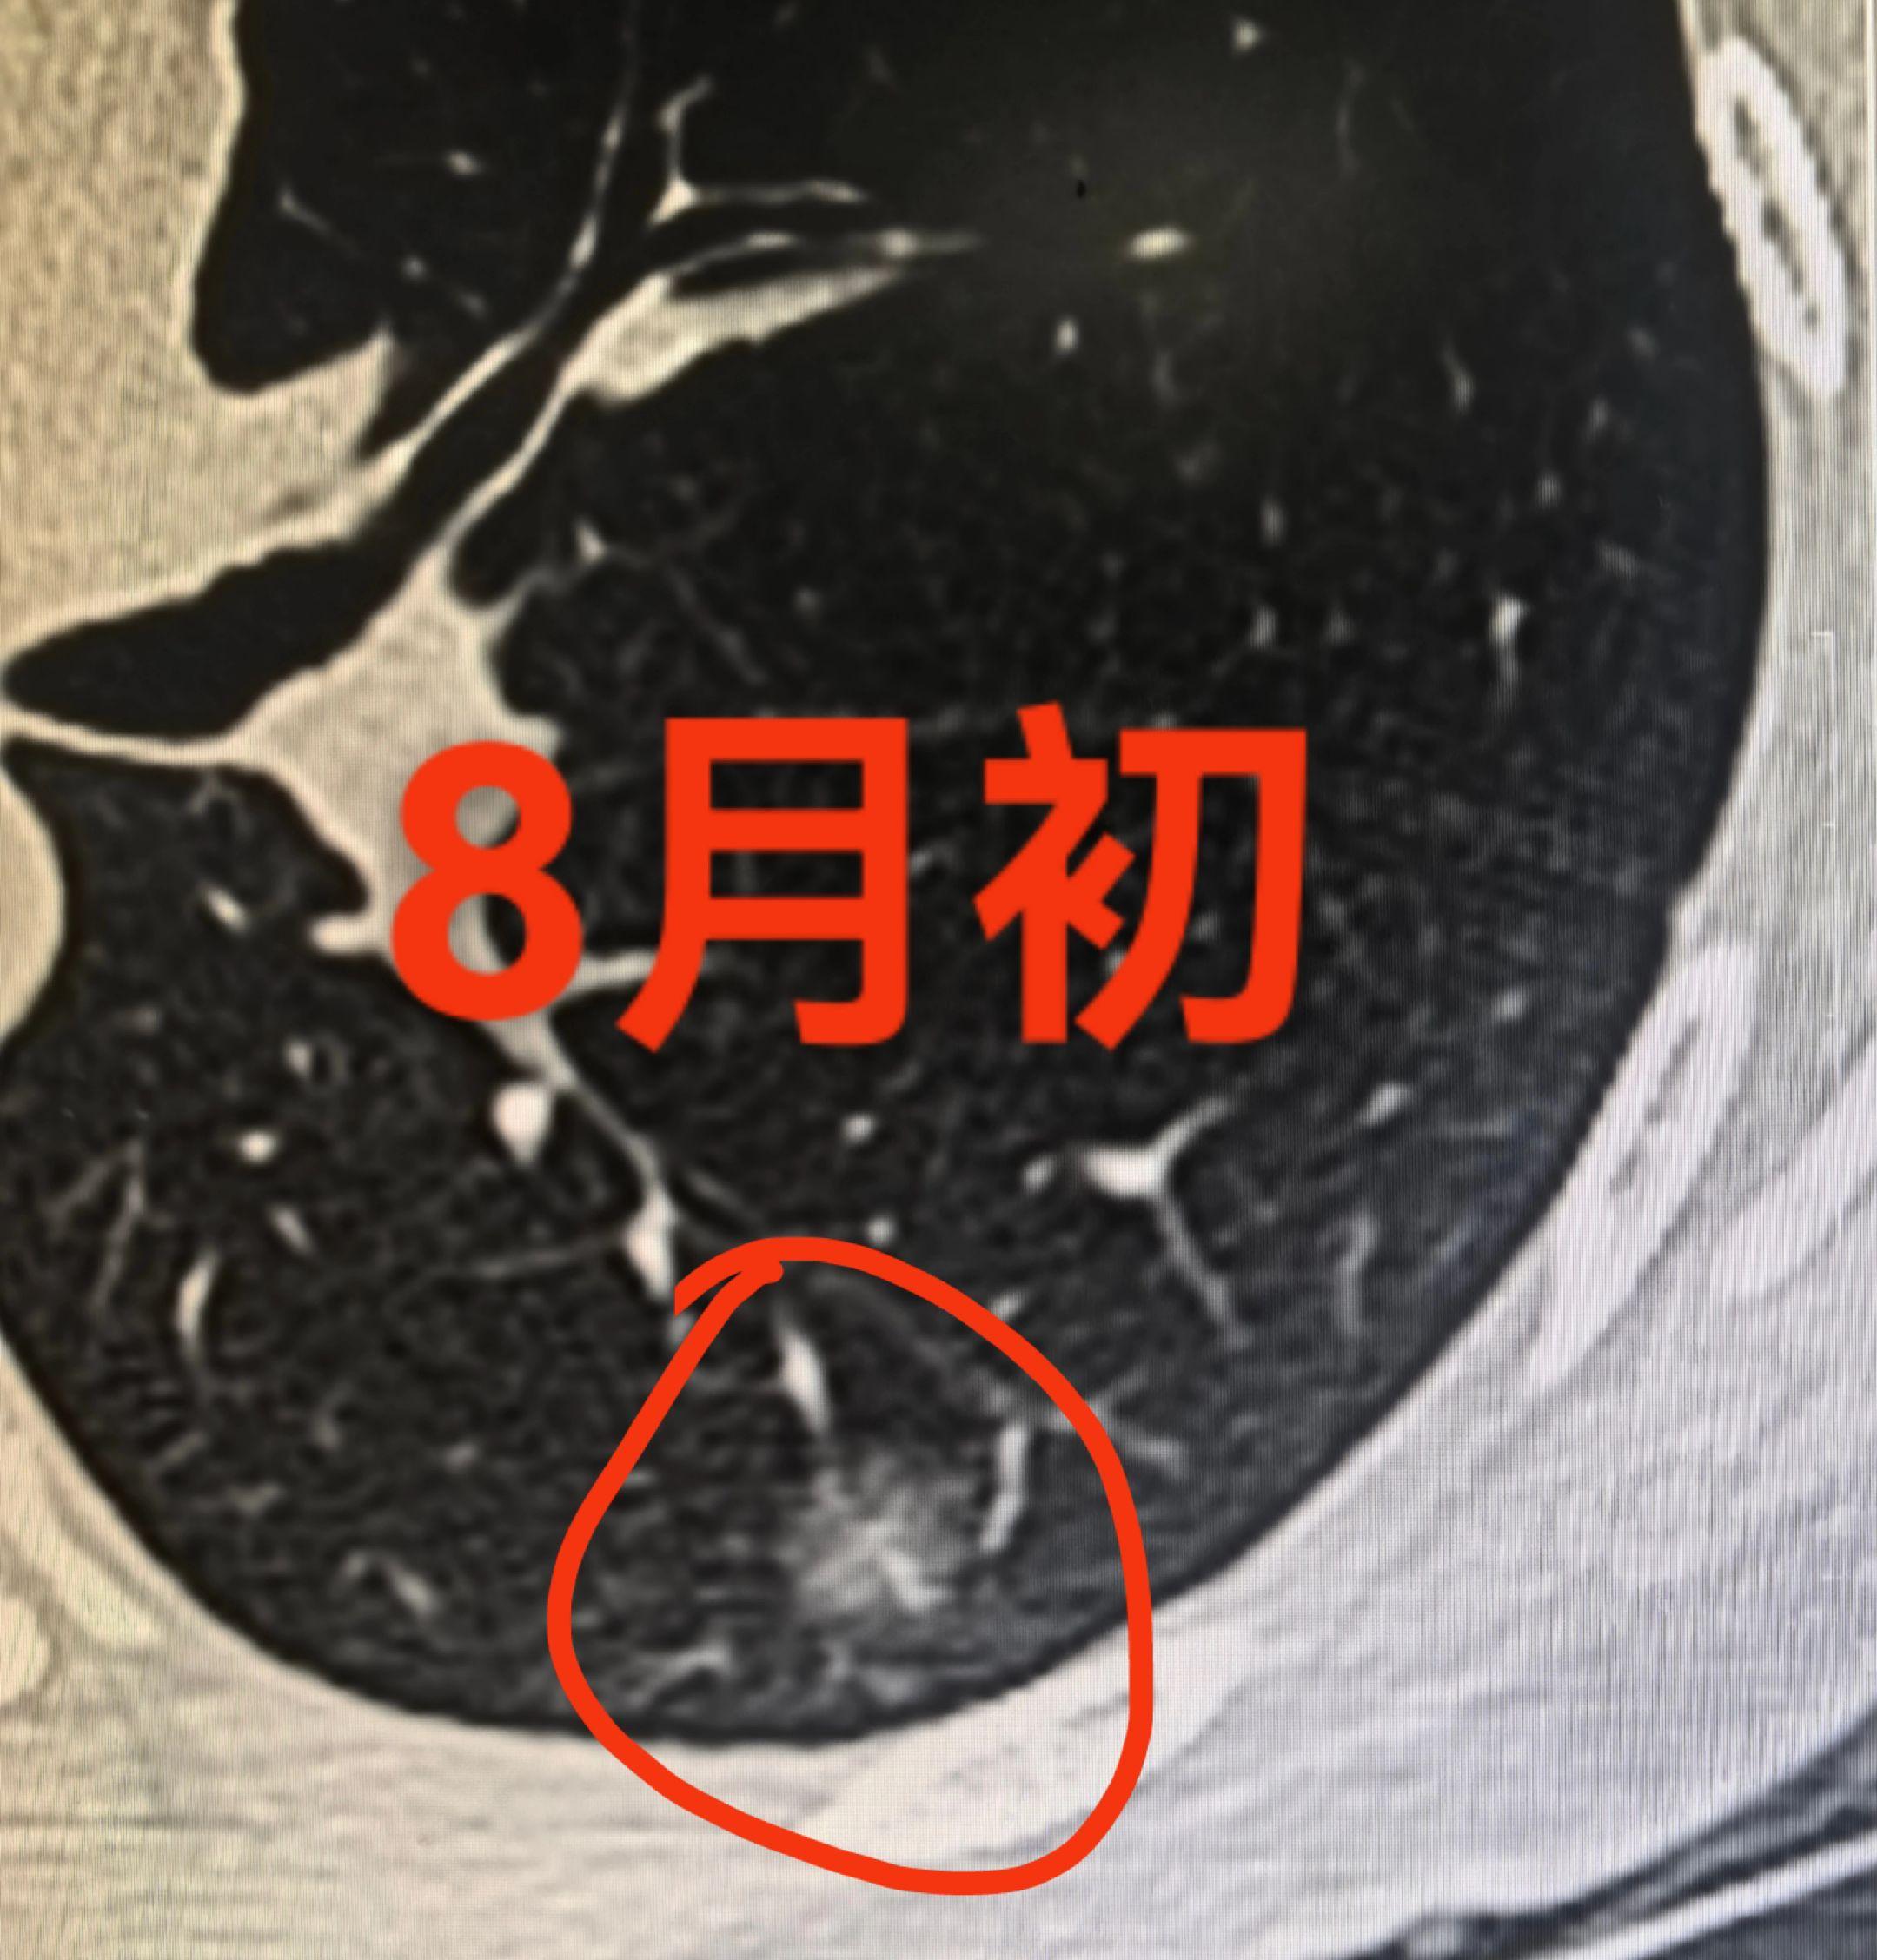

早期肺癌。

2025-08-10 04:45:55

呼吸的小超人